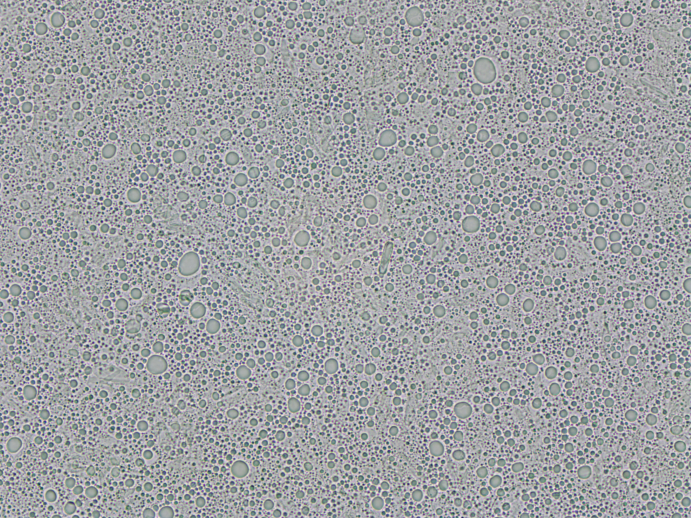

梓夢科技顯微鏡法粒度分析儀ZML310則采用高分辨率光學成像技術,能夠直接捕捉到顆粒的清晰微觀圖像。操作人員通過儀器配備的2000萬像素高清相機,可直觀觀察到顆粒的大小、形狀、表面顏色等細節特征,無論是球形、異形,還是粘連、團聚的顆粒,都能清晰呈現。同時,結合專業的顯微圖像分析軟件,儀器可對顆粒的粒度進行精準測量,包括粒徑、粒徑分布、等效直徑等多項參數。這種 “直觀觀察 + 精準測量” 的模式,實現了粒度與形態的雙重檢測,避免了激光粒度儀因無法識別形態而產生的誤判。在醫藥行業的粒度檢測中,梓夢科技顯微鏡法粒度分析儀ZML310能清晰分辨出不同形態的顆粒狀態,準確測量其粒度,可清晰展示各類形態顆粒的占比情況,為優化制劑工藝提供更全面、可靠的依據。